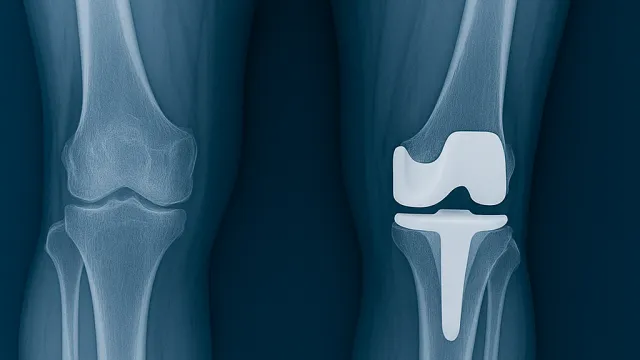

Robotik Diz Protezi Ameliyatı: Klasik Yöntemden Farkı Nedir?

Diz kireçlenmesi (diz osteoartriti), eklem kıkırdağının aşınması sonucu ağrı, hareket kısıtlılığı ve yaşam kalitesinde ciddi düşüşe yol açar. İleri ev...